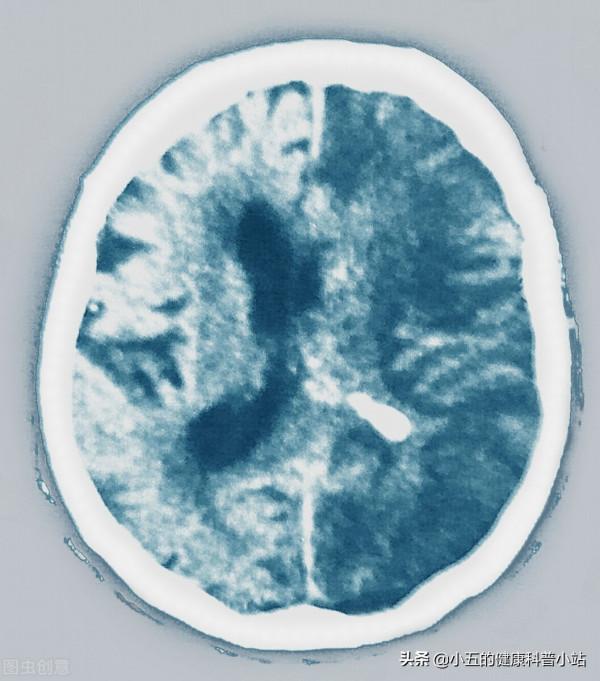

房顫時心房喪失收縮功能,血液容易在心房內淤滯而形成血栓,血栓脫落後可隨著血液流至全身各處。根據統計房顫患者出現腦卒中的機率是沒有房顫患者的15-20倍,2003年底我國發表了中華醫學會組織的中國除西藏以外大陸內地40家醫院近萬人1999~2001年房顫的回顧性研究結果表明房顫患者中腦卒中的發病率為17.5%,其中42.3%恢復功能‚49.7%中、重度致殘‚8.0%死亡。其次,房顫的患者還容易誘發肢體動脈栓塞,也就是血栓進入肢體動脈中造成動脈栓塞,肢體動脈栓塞的患者會出現突發性的劇烈疼痛,伴有肢體快速腫脹,嚴重時甚至發生肢體缺血性壞死,要截肢才能徹底治療。